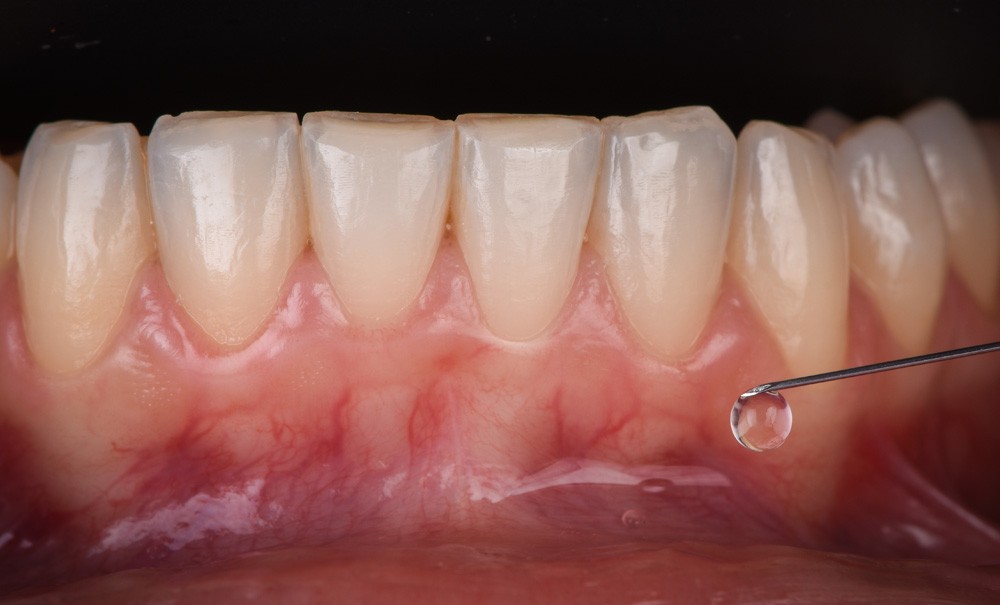

- Trans-muqueuse (anesthésie de surface ou de contact) (fig. 1).

- Sous-muqueuse (voie d’injection parentérale par infiltration).